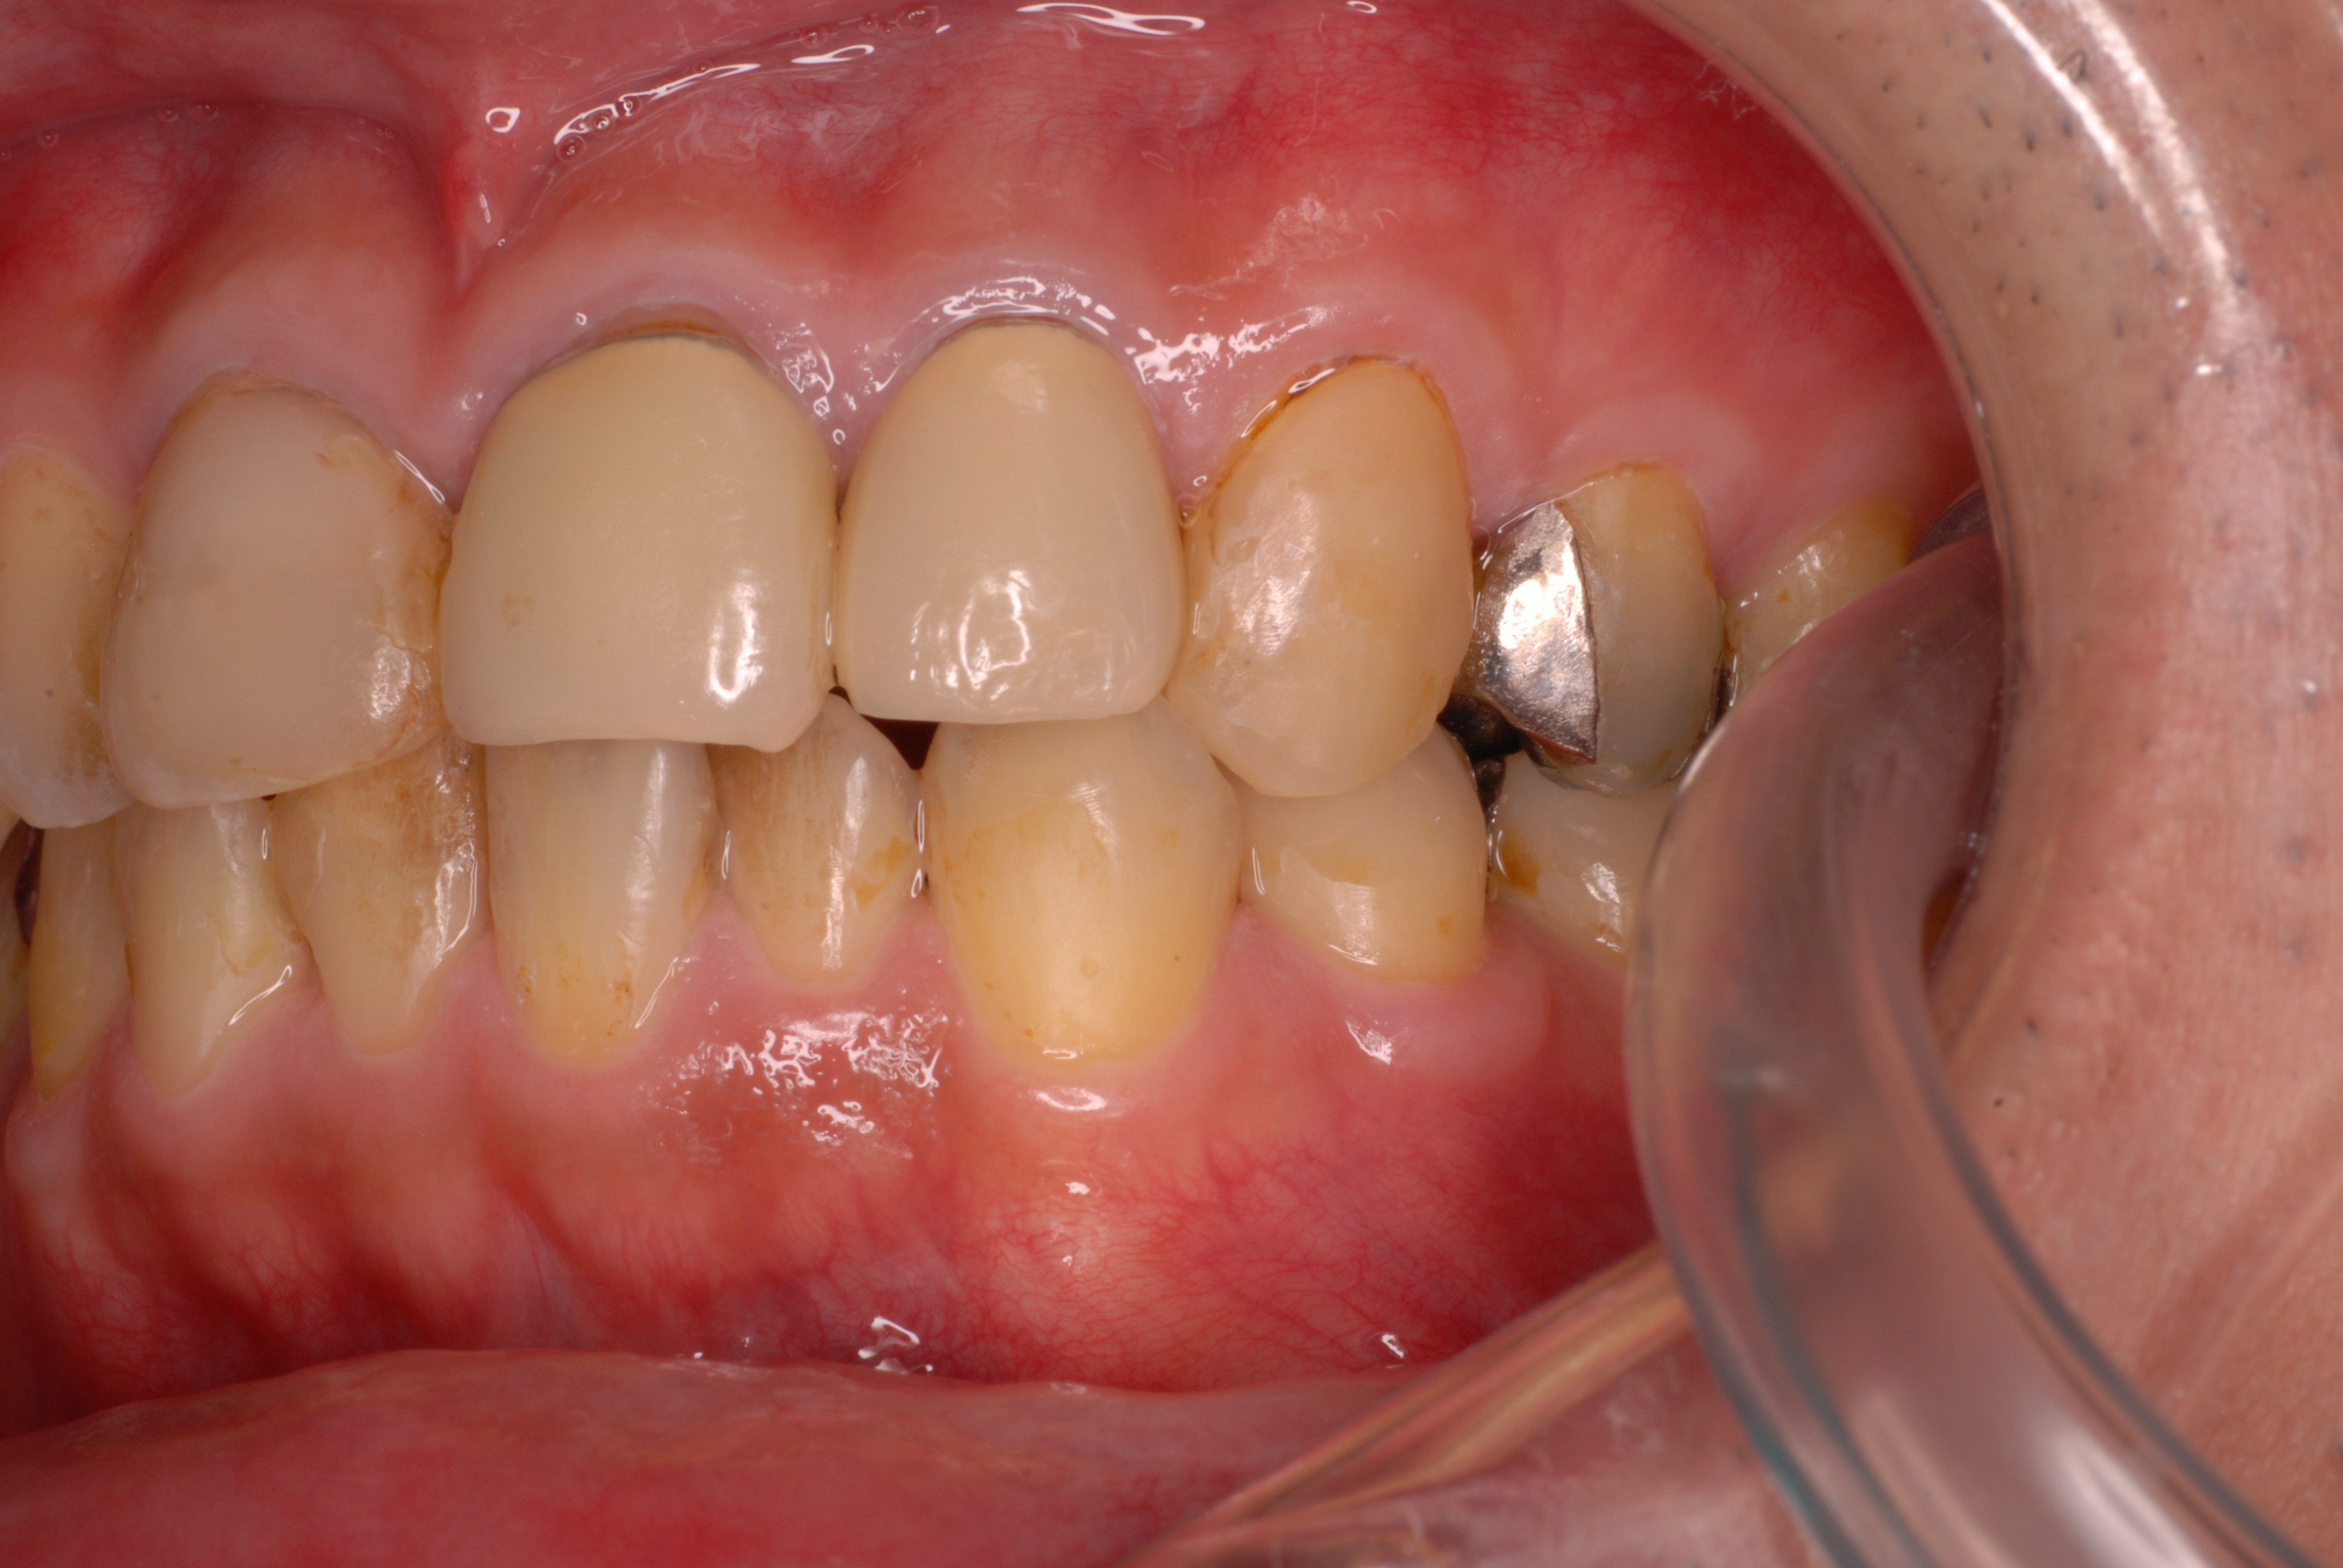

下の写真の方は虫歯と歯の間の歯周病が酷かったのです。

虫歯の治療も完全にできませんし、歯の位置が悪く又重なっている為に歯周病が治らずに説得に数カ月を有した後に矯正することになりました。